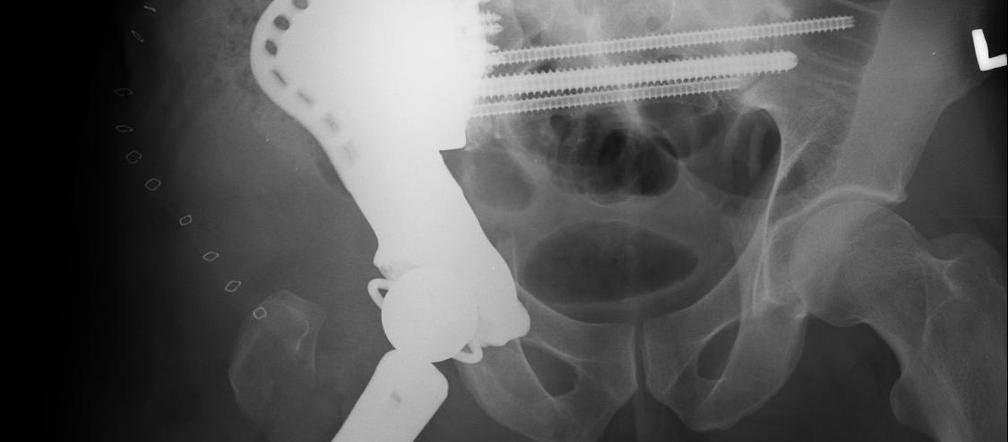

Lekarze z Kliniki Ortopedii Ogólnej, Onkologicznej i Traumatologii Szpitala im. W. Degi w Poznaniu przeprowadzili innowacyjną operację u 36-letniego pacjenta z nowotworem miednicy. We współpracy z amerykańskimi specjalistami stworzyli dla chorego jeden z największych dedykowanych implantów, jaki kiedykolwiek wszczepiono w Europie. Po przebytej operacji mężczyzna rozpoczął już proces rehabilitacji i na nowo uczy się chodzić.

Trudność operacji wynikała z rozległości zmian nowotworowych, a jej innowacyjność i wyjątkowość polegała na wykonaniu rekonstrukcji funkcji połowy miednicy i stawu biodrowego z użyciem bardzo dużego implantu wykonanego specjalnie dla pacjenta na podstawie badań obrazowych.

Po konsultacjach medycznych lekarze z Kliniki Ortopedii Ogólnej, Onkologicznej i Traumatologii postanowili uratować kończynę. Kierujący zespołem onkologicznym dr med. Jacek Markuszewski podjął współpracę z amerykańską firmą specjalizującą się produkcji implantów, w rezultacie czego na podstawie badań obrazowych wspólnie najpierw zaprojektowano, a następnie wykonano specjalną endoprotezę będącą dokładnym odwzorowaniem kształtu i wielkości miednicy pacjenta. Implant zastępuje połowę miednicy i staw biodrowy umożliwiając ponownie chodzenie.

Innowacyjność projektu endoprotezy polegała na wiernym odtworzeniu anatomii miednicy i dokładnej lokalizacji stawu biodrowego względem mięśni działających na staw. Nowatorski sposób połączenia implantu z kością umożliwił trwałe „biologiczne” połączenie z kością i zachowaniu funkcji układu nerwowego.

Jak podkreśla prof. Jacek Kruczyński, trudność operacji polegała na „doczepieniu” endoprotezy do pozostałej drugiej połowy miednicy pacjenta. Wybrano innowacyjne mocowanie długimi śrubami poprzez kość krzyżową, która zawiera struktury układu nerwowego. Dzięki zastosowaniu specjalnych przymiarów, wykonanych na podstawie tomografii komputerowej nie naruszono żadnych struktur układu neurologicznego, co jest zwykle jest typowym powikłaniem w tego typu zabiegach.